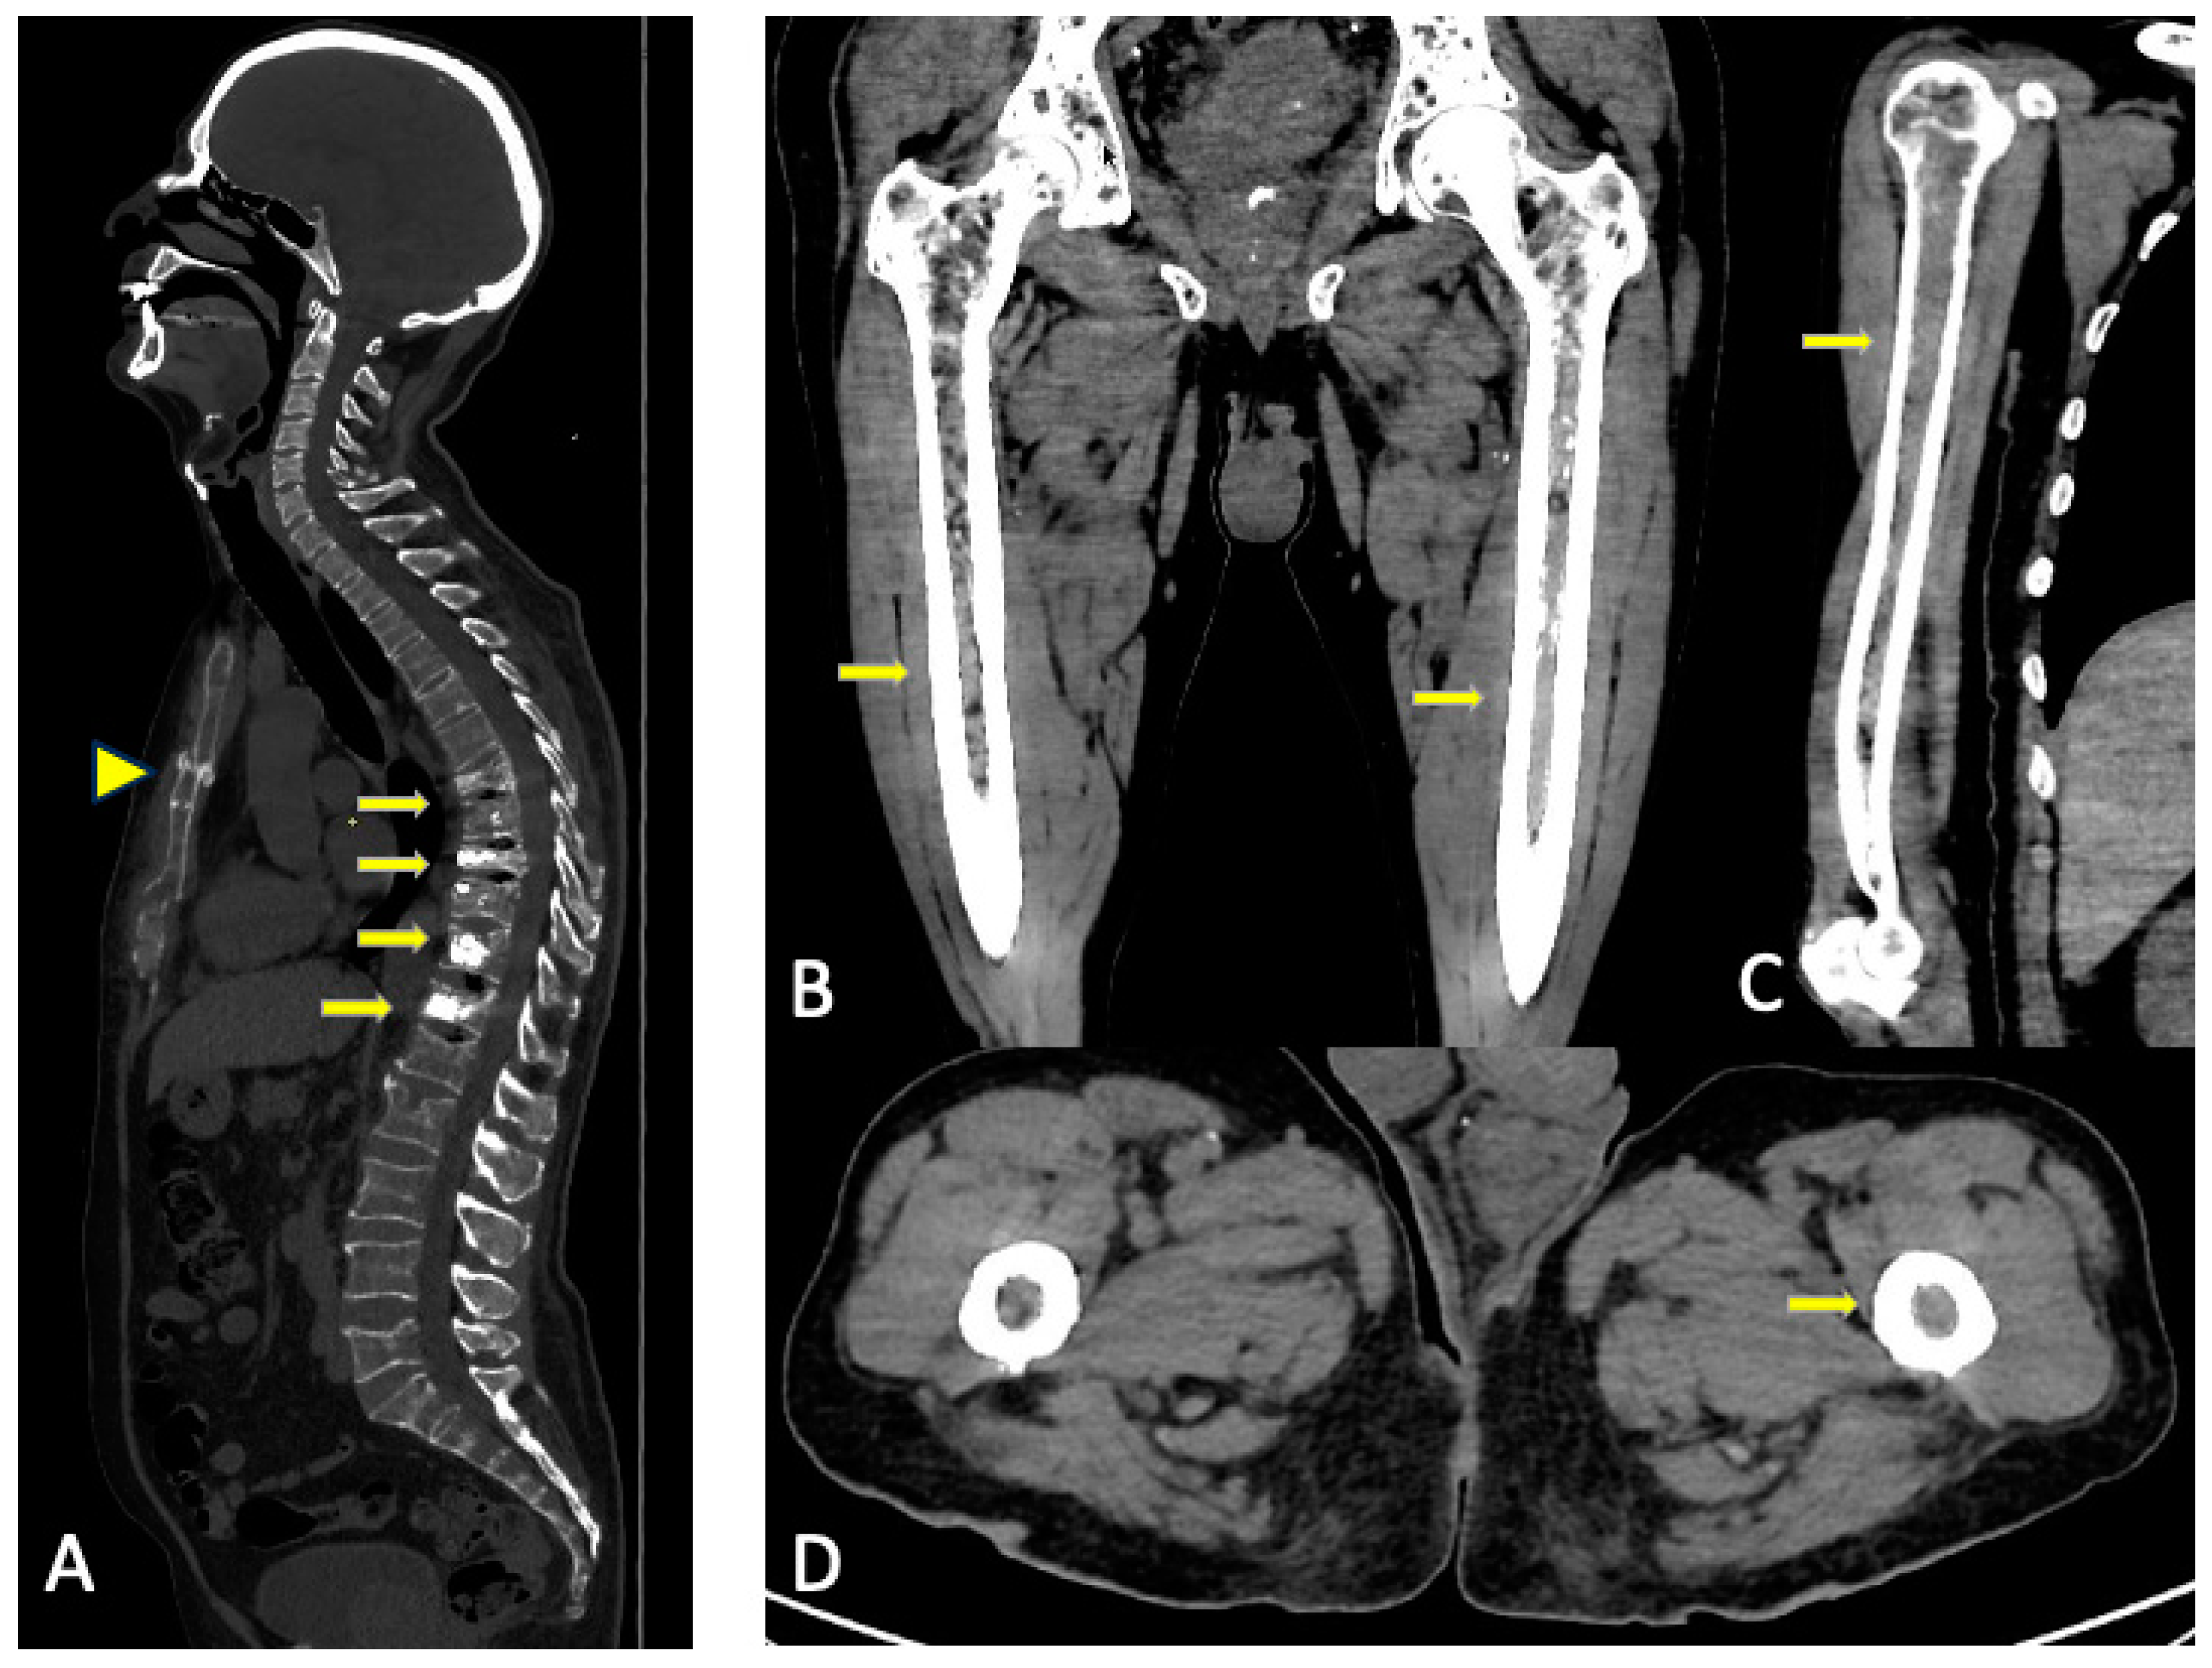

9. Complications